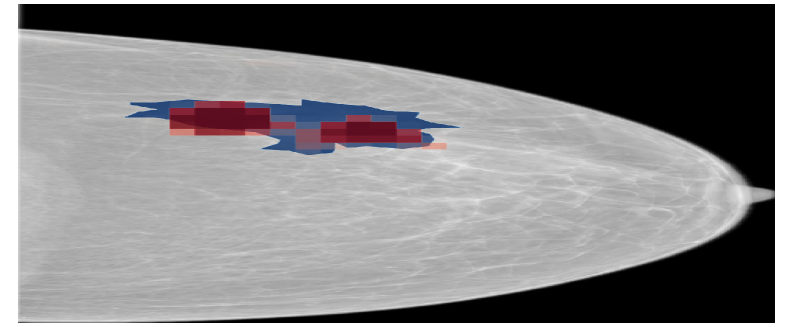

Refer to caption

(a) NYUtr\mathcal{M}_{\mathrm{NYU}}^{\mathrm{tr}}

(b) HCTPtr\mathcal{M}_{\mathrm{HCTP}}^{\mathrm{tr}}

(c) HCTP(BNFC)tr\mathcal{M}_{\mathrm{HCTP(BNFC)}}^{\mathrm{tr}}

Figure 12: Saliency maps generated by NYUtr\mathcal{M}_{\mathrm{NYU}}^{\mathrm{tr}}, HCTPtr\mathcal{M}_{\mathrm{HCTP}}^{\mathrm{tr}}, HCTP(BNFC)tr\mathcal{M}_{\mathrm{HCTP(BNFC)}}^{\mathrm{tr}} models a sample from the HCTP dataset. Blue regions represent the ground truth annotations, while red regions highlight the saliency maps corresponding to the malignant class.

The saliency map in Figure 12 further supports these findings, showing that HCTP(BNFC)HCTPtr\mathcal{M}_{\mathrm{HCTP(BNFC)}\rightarrow\mathrm{HCTP}}^{\mathrm{tr}} highlights similar regions of interest as the fully fine-tuned model (HCTPtr\mathcal{M}_{\mathrm{HCTP}}^{\mathrm{tr}}).